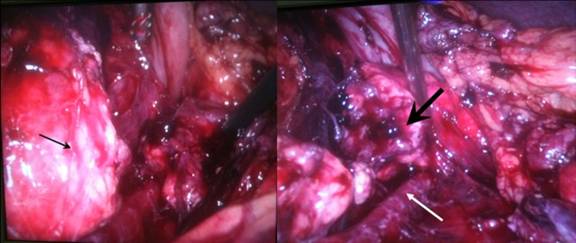

We performed a laparoscopic exploration the following day. The trocars were placed as following: a supra-umbilical 10 mm port, and three 5 mm ports in the left subcostal region, the right hypochondrium, and below the xyphoid appendix. The abdominal exploration disclosed a minimal hepatic contusion of the left lobe without active bleeding, the absence of associated hollow viscus injury, and a moderate hemoperitoneum. Then, the lesser sac was opened through the gastrocolic ligament, preserving the short gastric vessels, but especially the left gastroepiploic artery, which represents the main collateral vasculature in case of spleen preservation with splenic vessels resection [11, 12]. The pancreas was shown to be transected entirely at the level of its tail, with significant peripancreatic hematoma and inflammation. The splenic vein was identified deep behind the pancreas (Figure 2). We could perform a totally laparoscopic distal pancreatectomy with spleen and splenic vessels preservation. The proximal main pancreatic duct was oversewn with 4-0 Monocryl® (Ethicon, Inc., Somerville, NJ, USA), with no further treatment of the proximal pancreatic margin. We placed a Penrose drain near the head of the pancreas. The resected piece was removed in a bag, by a short Pfannenstiel laparotomy (Figure 3). Indeed, it was necessary not to damage the tail of the pancreas, which was subsequently treated for islets isolation.

Figure 2. Operative view with the body of the pancreas (arrow) separated of the tail (thick arrow), and the splenic vein in depth (white arrow). |